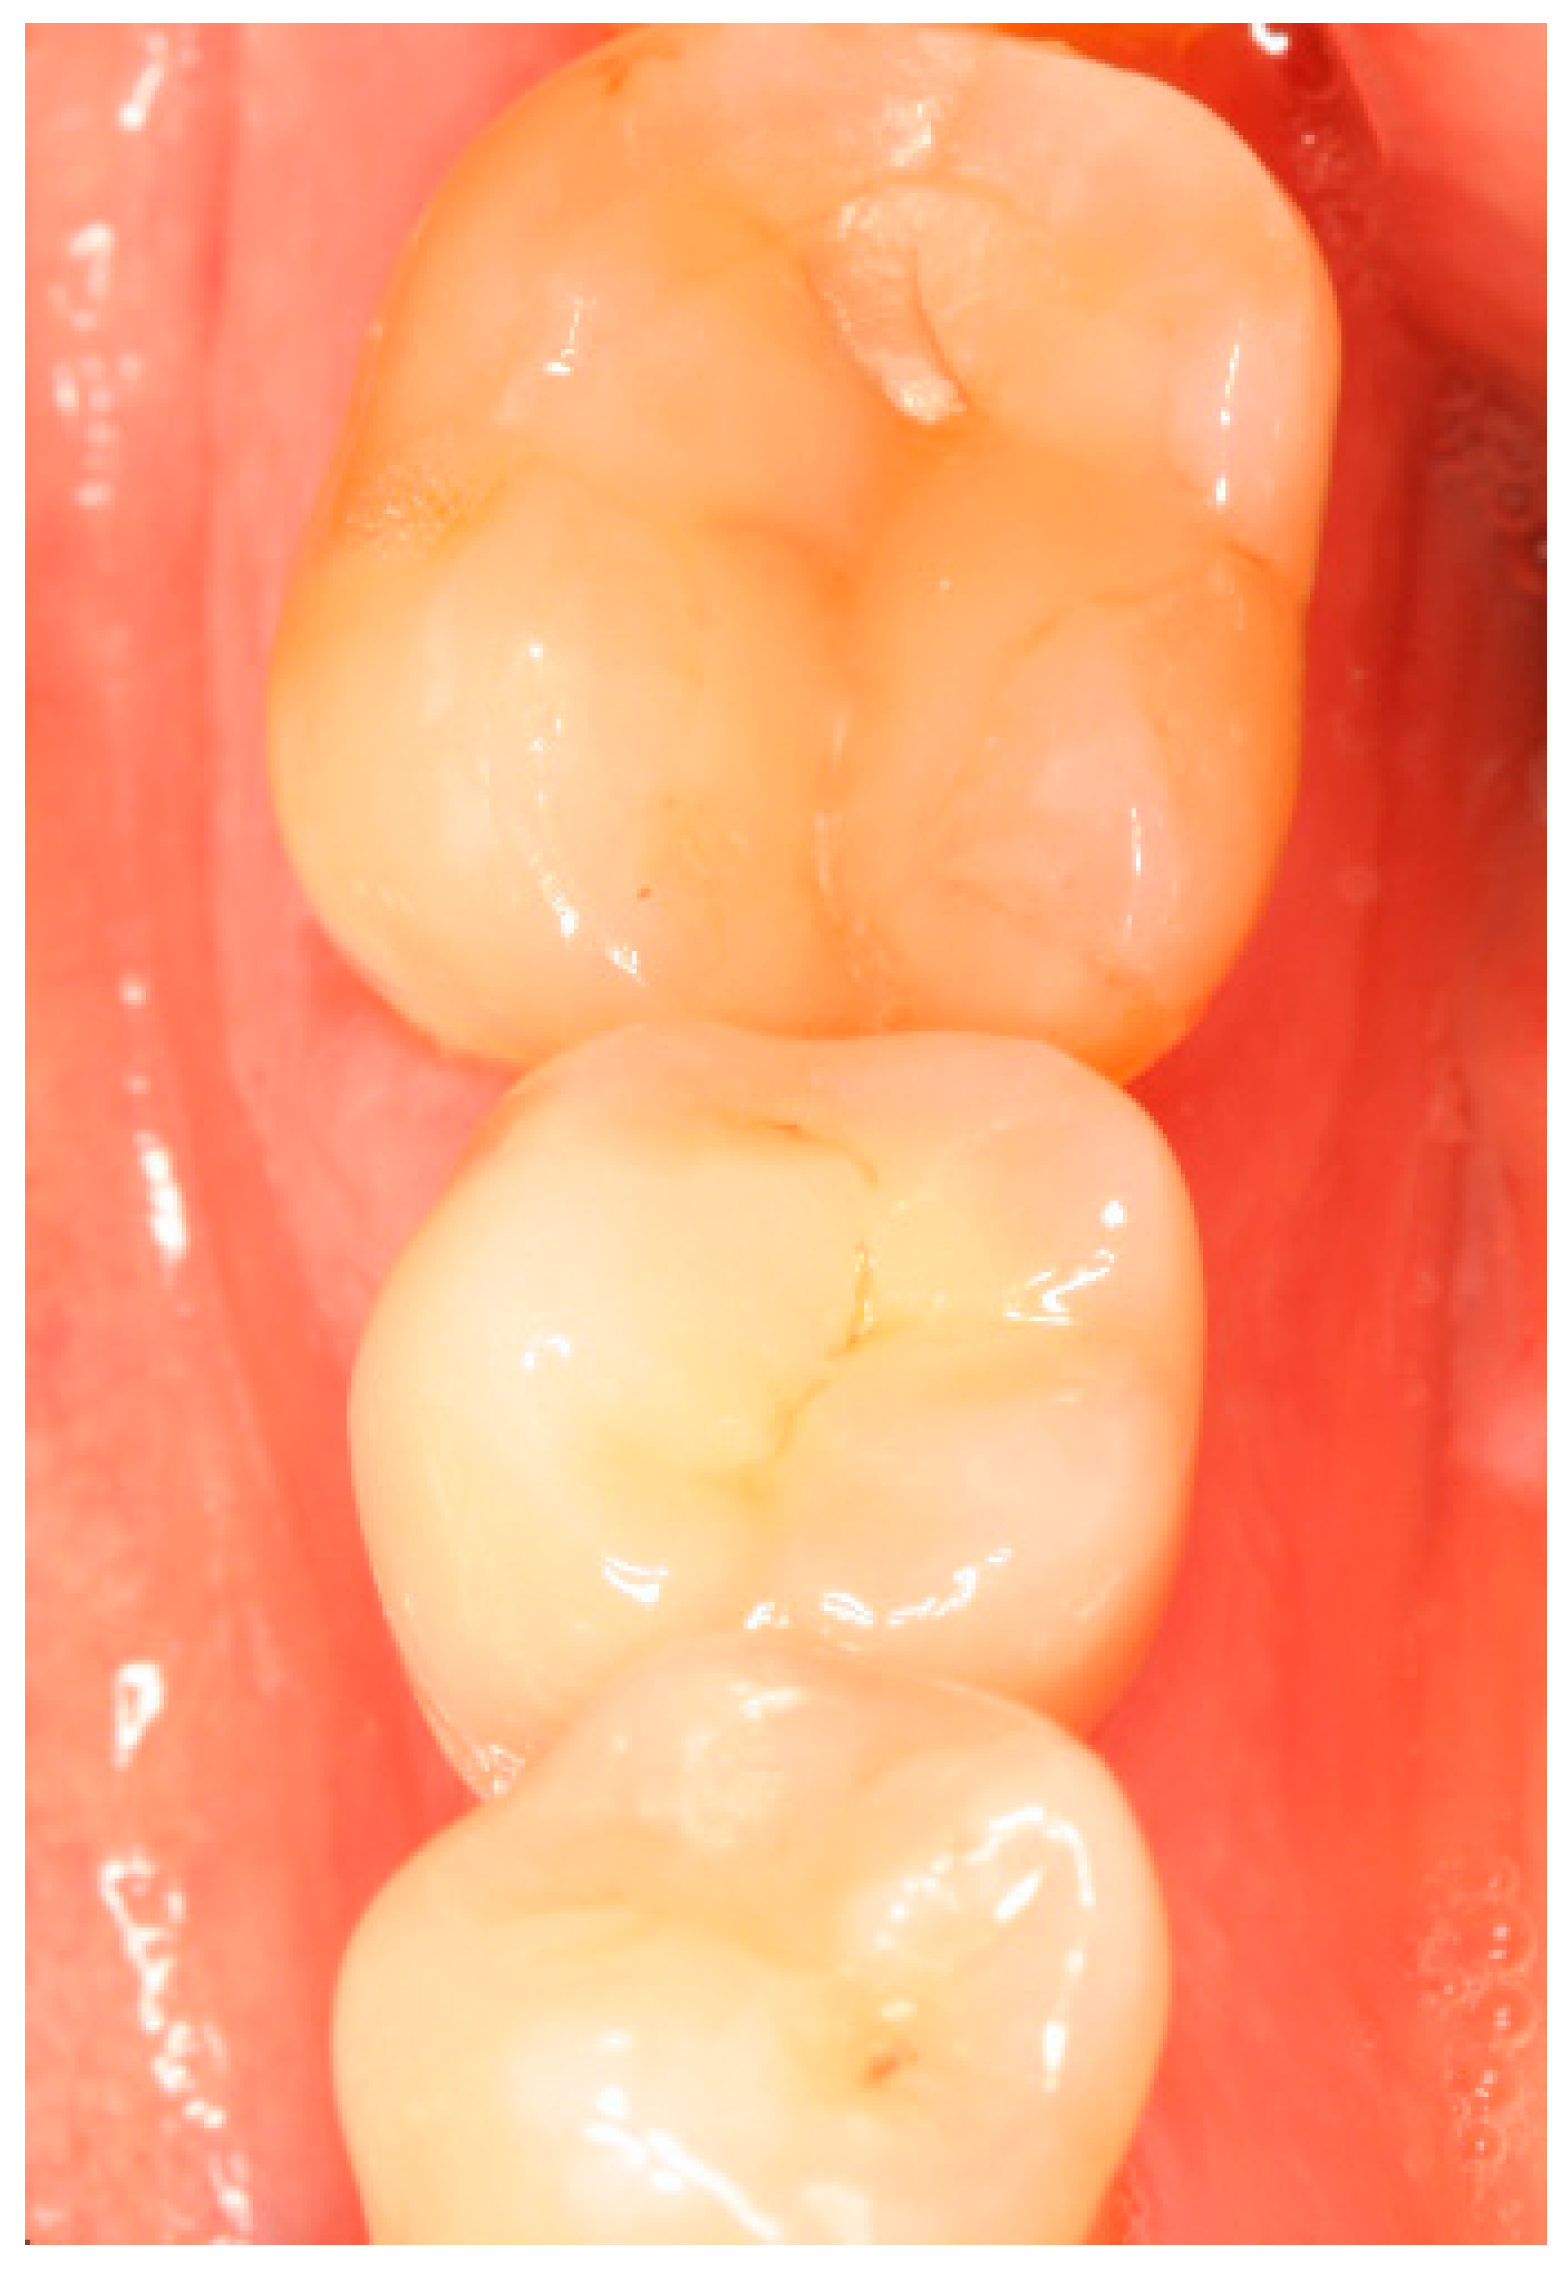

Situation after crwon cementation. Occlusal view.

Clinical situation at the 1-year follow-up. Occlusal view.

Clinical situation at the 3-year follow-up. Occlusal view.

Clinical situation at the 5-year follow-up. Occlusal view.